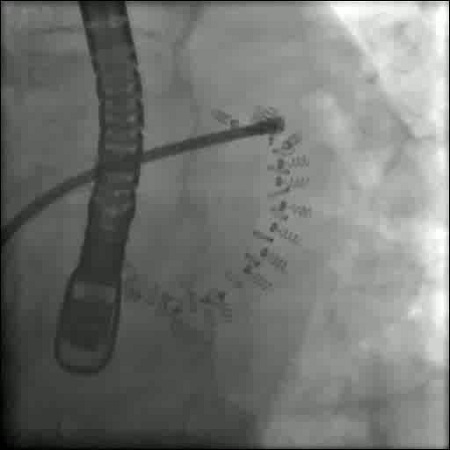

Mittels Katheter wurde der Herzklappenring mit 17 Ankern fixiert. © Klinikum Wels‐Grieskirchen